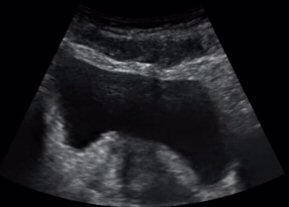

. ÃÖ±Ù ÃÊÀ½ÆÄ±â±â¸¦ ÀÌ¿ëÇÏ¿© ½Ç½Ã°£ÀûÀ¸·Î

ÄÚ¾î ±ÙÀ°À» °üÂûÇϸ鼭 ÄÚ¾î ±ÙÀ°À» ¿îµ¿½ÃŰ´Â ¹æ¹ýÀÌ ´ëµÎµÇ¾î ¿Ü±¹¿¡¼­ À̹Ì

³Î¸® ½ÃÇàµÇ°í ÀÖ½À´Ï´Ù

5)  ÄھƱÙÀ°À̶õ?